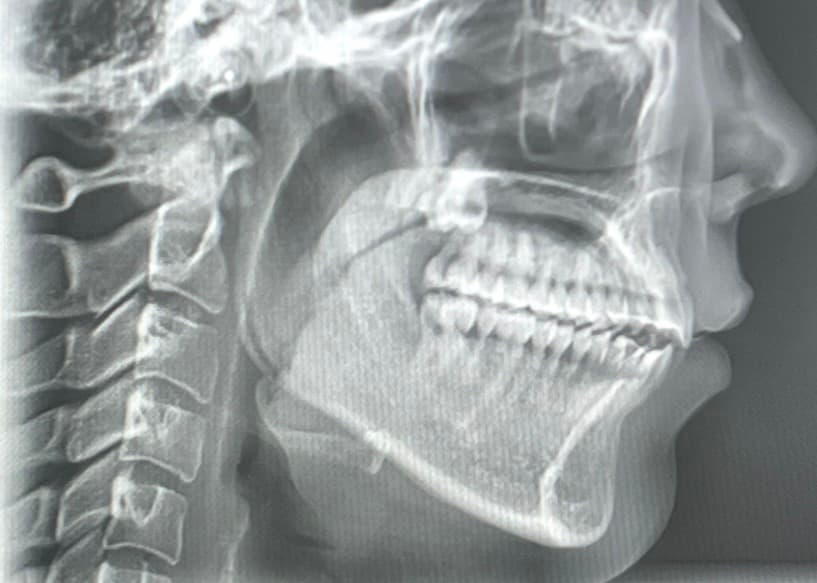

제가 19~21년 치아교정하고 정말 예쁜 교합으로 잘 지내다가 올해 3월 초에 질긴 음식을 먹고 3월 중순 쯤 자고 일어났더니 오른쪽 턱관절이 뒤로 밀려서 (회전해서),개방교합이 생겼습니다. 디스크 쪽 불편함도 있어서 구강내과 치료도 받다가 호전이 없어 구강악안면외과에 갔더니 제가 턱 사이즈가 작은데 , 턱이 뒤에 있어야 편한 위치인데 치아교정은 앞에서 물리게 해놔서 질긴 음식 먹은 충격으로 인해 뒤로 밀린거라 하셔서 하악 수술을 하라고 했는데 아무리 생각해도 너무 의아해서요. 턱 사이즈가 작다고 어느날 이렇게 뒤로 밀리는 일이 생기나요? 저는 아무리 봐도 디스크가 어긋나서 막고있는 것 같아요 CR CO Discrepancy를 언급하시던데 저는 치아교정한 교합으로 정말 편하게 지냈거든요

사진은 순서대로 턱 뒤로 회전하기 전,후입니다.

• 2번 째 사진

3. 현재 엑스레이 사진상으론 어금니 교합은 정상적입니다. 치아 교합보다는 턱관절 문제에 집중해봐야 할 것 같습니다